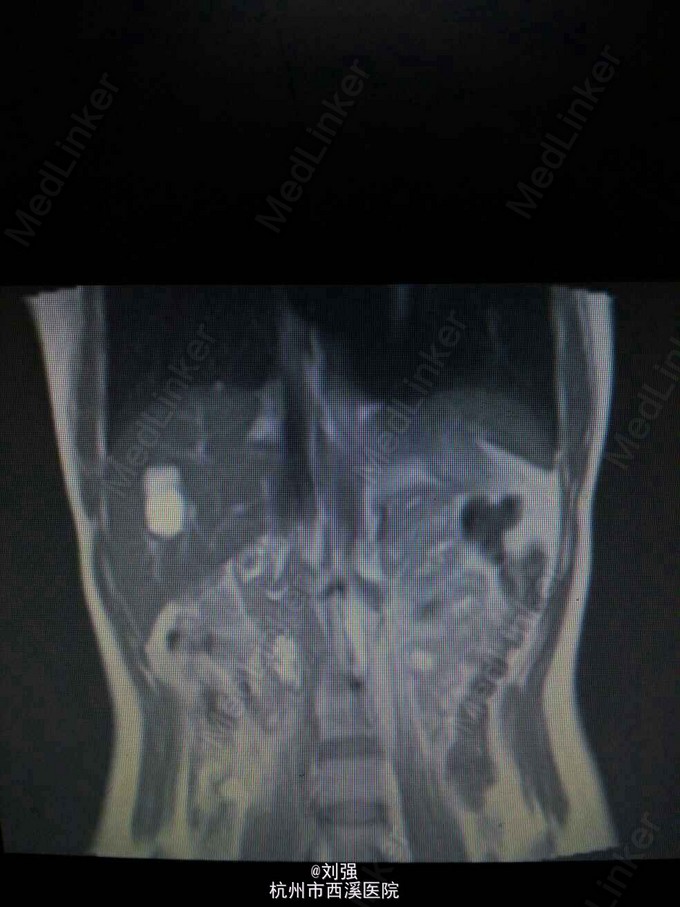

患者40岁女性,因“肝区疼痛2月余,加重10余天”入院。1个月前到外院就诊,腹部CT提示肝S5血管瘤。既往有"胃溃疡"病史。余病史无特殊。

查体:生命体征平稳,心肺无特殊。腹部外形正常,腹式呼吸存在,无压痛以及反跳痛,肝区叩击痛阳性。辅助检查:实验室检查提示白蛋白下35.97g/L。腹部彩超提示:肝S5一大小为4.3cmX3.5cm实质性病灶,考虑血管瘤。腹部MRI检查提示S5段血管瘤。